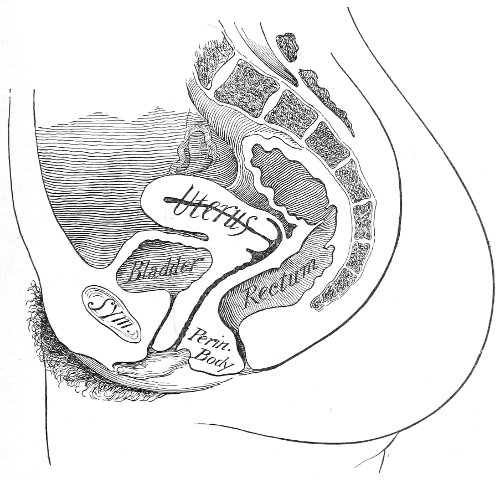

Vaginal and Bimanual Examination.—Having examined and noted the condition of the external genitals, the physician should next proceed to examine the vagina. The index finger of the right or the left hand should be gently introduced into the vagina. The condition of the vaginal walls, and the direction, consistency, form, etc. of the vaginal cervix, may be determined. The shape and size of the os uteri should be noted. The ulnar edge and the tips of the fingers of the other hand should then be placed upon the abdomen, immediately above the symphysis pubis, and gently pressed backward and downward toward the vaginal finger 24 (Fig. 2). In this way the various pelvic organs, the uterus, Fallopian tubes, ovaries, and ureters, may be palpated between the two hands, and their position, size, shape, and consistency may be determined. Such an examination is, of course, made much more easily in a thin woman than in a fat one. A thin woman a few weeks after labor may be examined most easily, on account of the relaxation of the abdominal and vaginal walls.

This is called the bimanual method of examination, and the student will find that as he acquires practice in this method he will gradually depend less upon examination by the uterine sound and the speculum, and will rely altogether upon his sense of touch, his ability to palpate.

In making the bimanual examination the structures 25 should be palpated methodically in order. The vaginal finger notes the condition of the cervix uteri. If the fundus be in the normal position, the uterus can then be taken between the abdominal hand (upon the fundus) and the vaginal finger (upon the cervix) (Fig. 3). The shape, size, mobility, and consistency are noted. The vaginal finger is then passed anteriorly and laterally toward either uterine cornu, while the abdominal fingers pass over to the posterior aspect of the same cornu. The ovarian ligament and the proximal end of the Fallopian tube may thus be felt. Passing farther outward, the whole of the tube and the ovary may be examined. The same procedure is then applied to the opposite side.

Fig. 3.—Bimanual examination; median sagittal section of the pelvis.